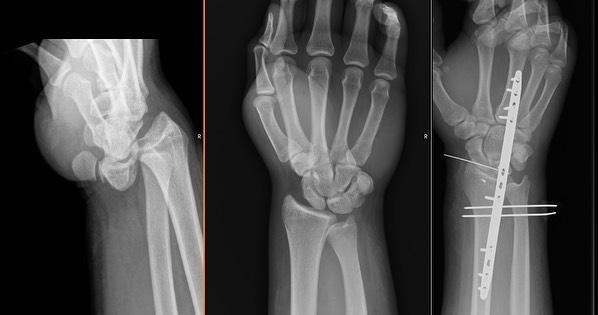

Las luxaciones radiocarpianas son lesiones raras que resultan de fuerzas de alta energía a través de la muñeca con el hallazgo distintivo de la ruptura del ligamento radiocarpiano. Los métodos de tratamiento publicados son completos con resultados de moderados a buenos. El propósito de este estudio fue revisar el tratamiento de las luxaciones radiocarpianas con una placa dorsal para la muñeca.

El tratamiento agudo con una placa de extensión dorsal de la muñeca en esta serie dio como resultado resultados comparables a lo que se informó anteriormente en la literatura. La placa de expansión dorsal de la muñeca ofrece al cirujano un método confiable de estabilización, con un mínimo de trauma quirúrgico adicional en la muñeca, al tiempo que evita la posibilidad de infecciones que se desarrollan con otros métodos de tratamiento.